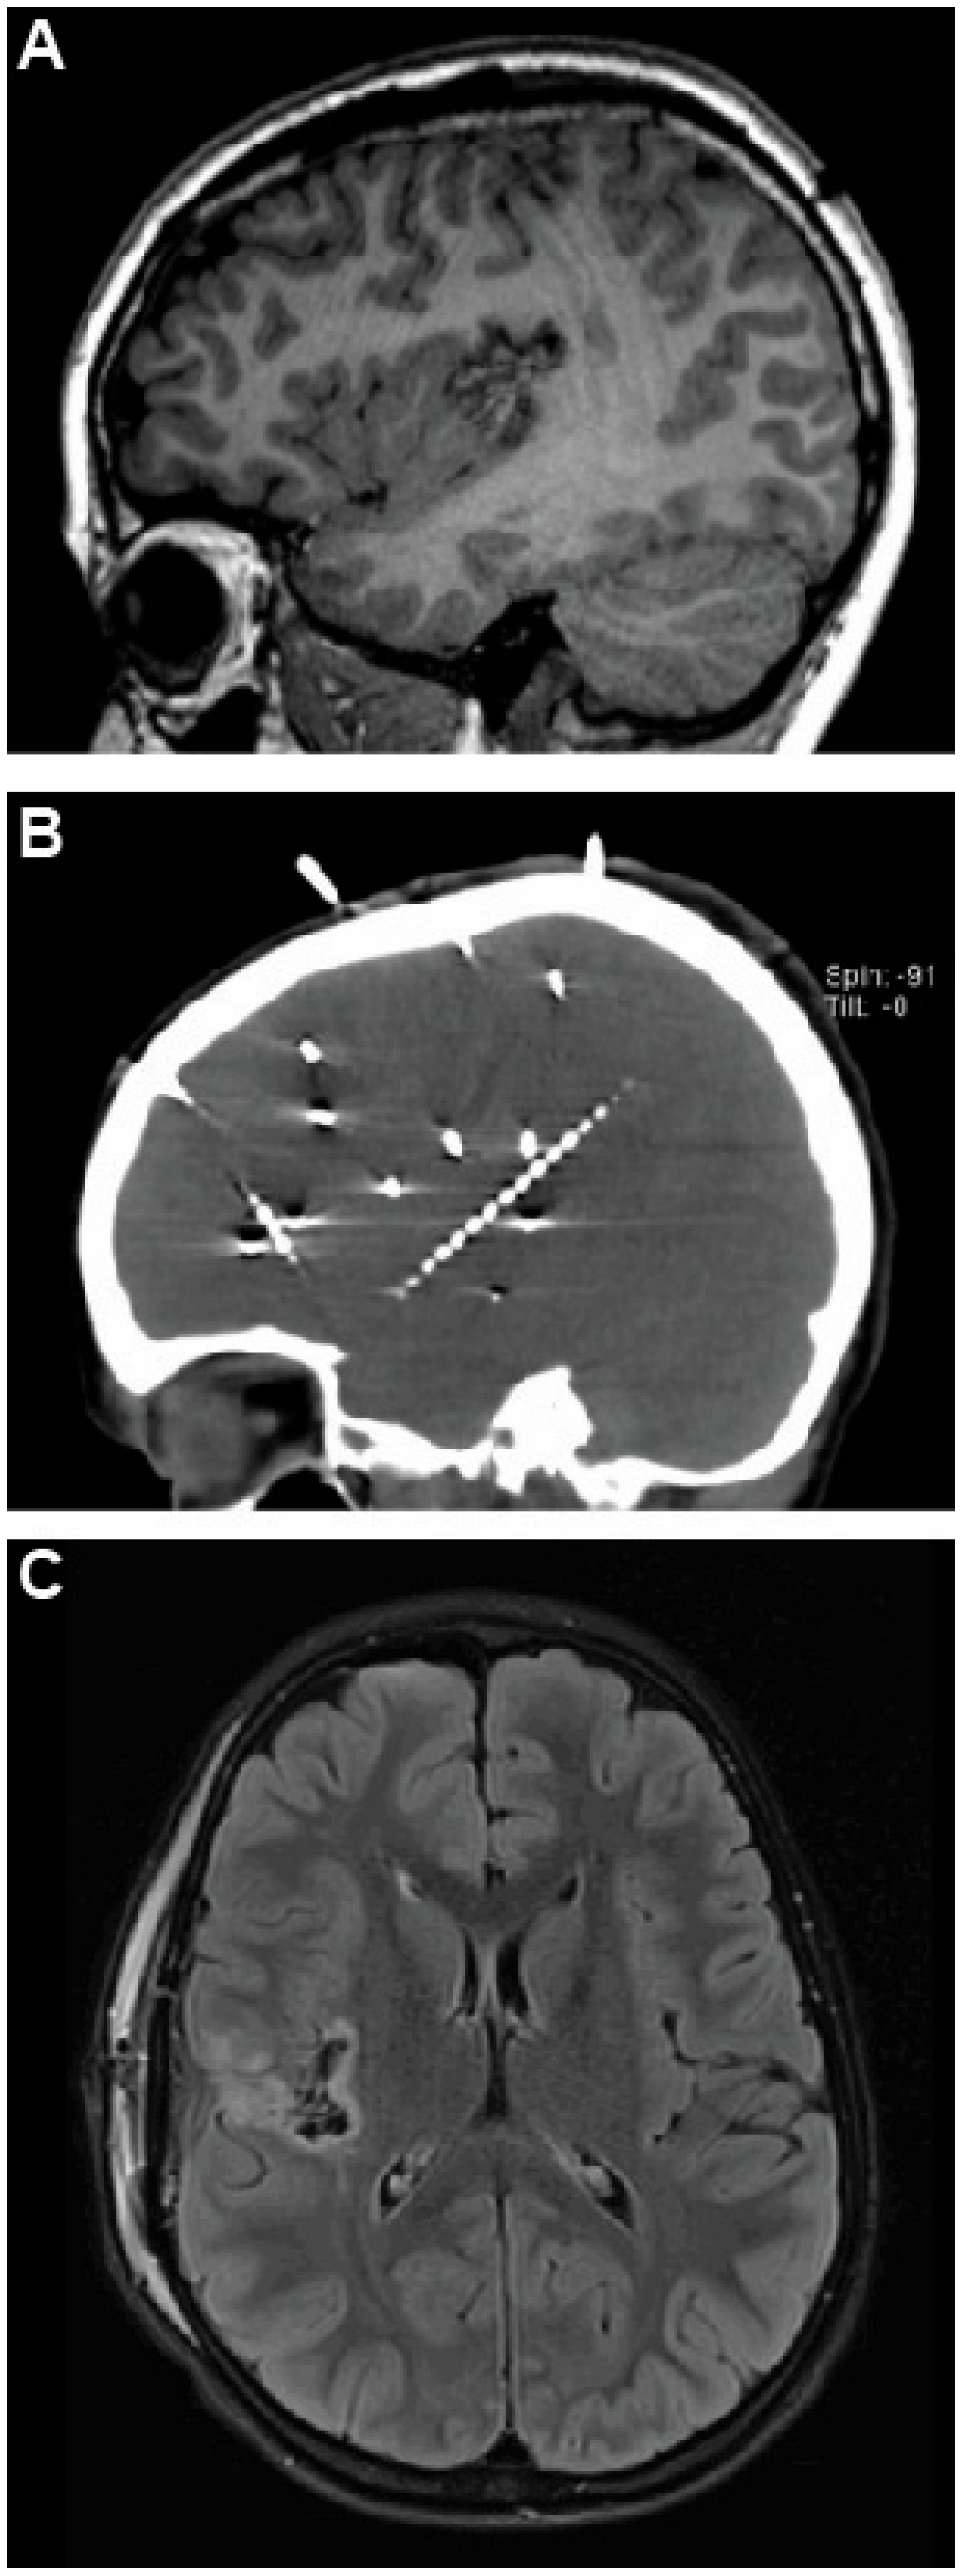

2.1. Case 1—Trans-Sylvian Approach for Insular Focal Cortical Dysplasia